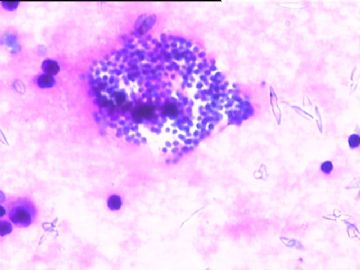

78y,男,胸水。 大家看看那些小于淋巴细胞的东东。

但,最后一图的组织细胞内吞噬现象,怎么解释。

离体的细胞在一定的时间内还是活细胞,所以我推测吞噬细胞可能还是有一定的吞噬功能的。不过,确实也不能就排除了在活体内的微生物感染的可能。结合临床应该能够得到一定程度的澄清。